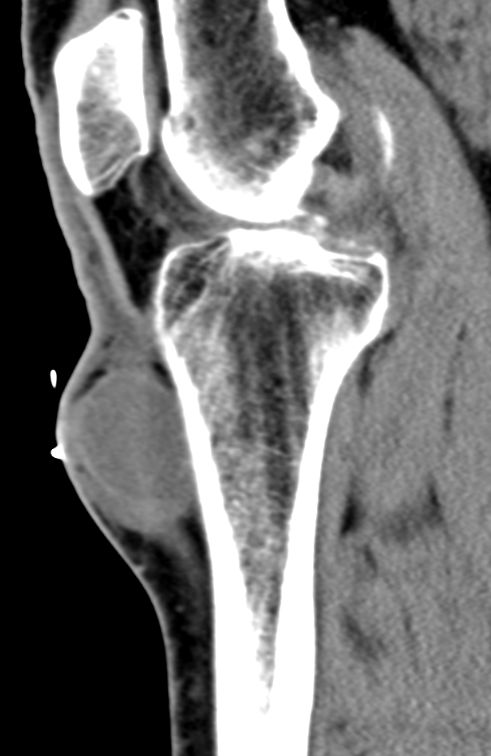

| Fall | CT: Rundliche, kapsulierte, glatt begrenzte RF an der proximalen Tibia medialseitig 3 cm.

Keine Infiltration der Haut oder der Tibia.![]() |